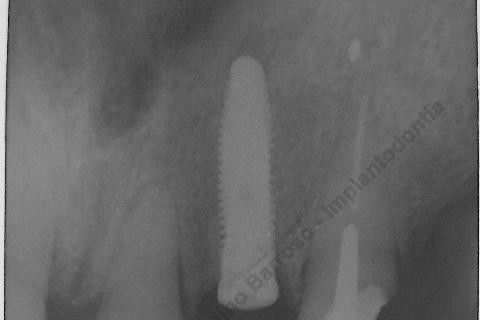

Inicalmente estava planejado um implante cone morse 3.5 X 15,0 EX, mas resolvi experimentar um implante HI oferecido pelo vendedor da Bionnovation, como brinde (ele soube que estou preferindo o cone morse mas não trabalham com este sistema), e não consegui carga imediata neste implante. O travamento não foi satisfatório, ficou com um pouco mais de 20 N, menos de 25 N. Apesar desta ocorrência isto não significa que dará problema, apenas não fiz com carga imediata, aguardaremos 4 meses para a osseointegração.

Se o implante utilizado fosse o CM EX 3.5 X 15,0, além deste tipo de implante possuir característica autorosqueante, promovendo pelo seu design um melhor travamento, o seu comprimento de 15mm + 2mm infraósseo, conseguiríamos 6 mm de travamento em osso "virgem" (comprimento da raiz era de 11 mm) e travaria na cortical nasal. Mas este que usei, hexágono interno cônico, fica ao nível do rebordo; o maior que fabricam (comprimento de 15 mm), não apoiou em osso cortical e não é autorosqueante como o EX da Neodent.